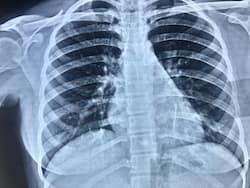

6 वर्षीय कनिष्का को जन्मजात हृदय दोष था, जिसका सफलतापूवर्क इलाज फॉन्टन सर्जरी की मदद से किया गया।

Open Heart Surgery: ओपन हार्ट सर्जरी एक ऑपरेशन है, जिसमें डॉक्टर छाती खोलकर दिल की बीमारियों जैसे ब्लॉकेज या वॉल्व प्रॉब्लम का इलाज करते हैं।